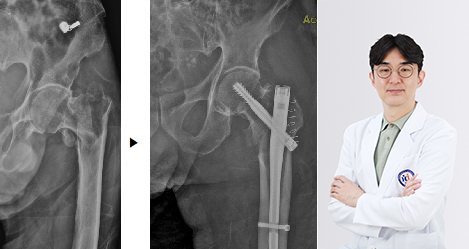

척추·관절센터